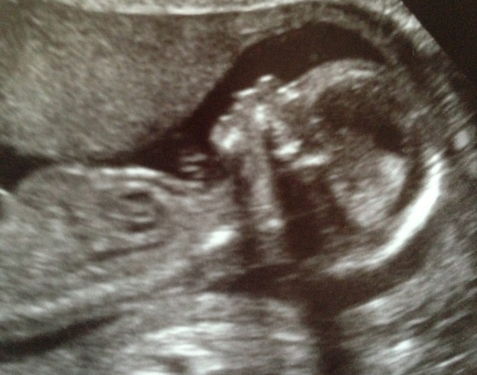

If anyone take a guess at my 12 week scan?

I think I see a nub right below the leg bone and it looks girl to me.

Thank you for your reply!! I kind of thought so too... interesting...

I was going to say girl, too, but I see your signature say's it's a boy. How do you know for sure? And what was the gestation in this pic?

Leaning girl x

At 16+5 weeks the tech said boy, I am not 100% convinced it was cause I only saw the nub no scrotum. All my others were very obvious, this one wasn't. Will find out in 10 days.